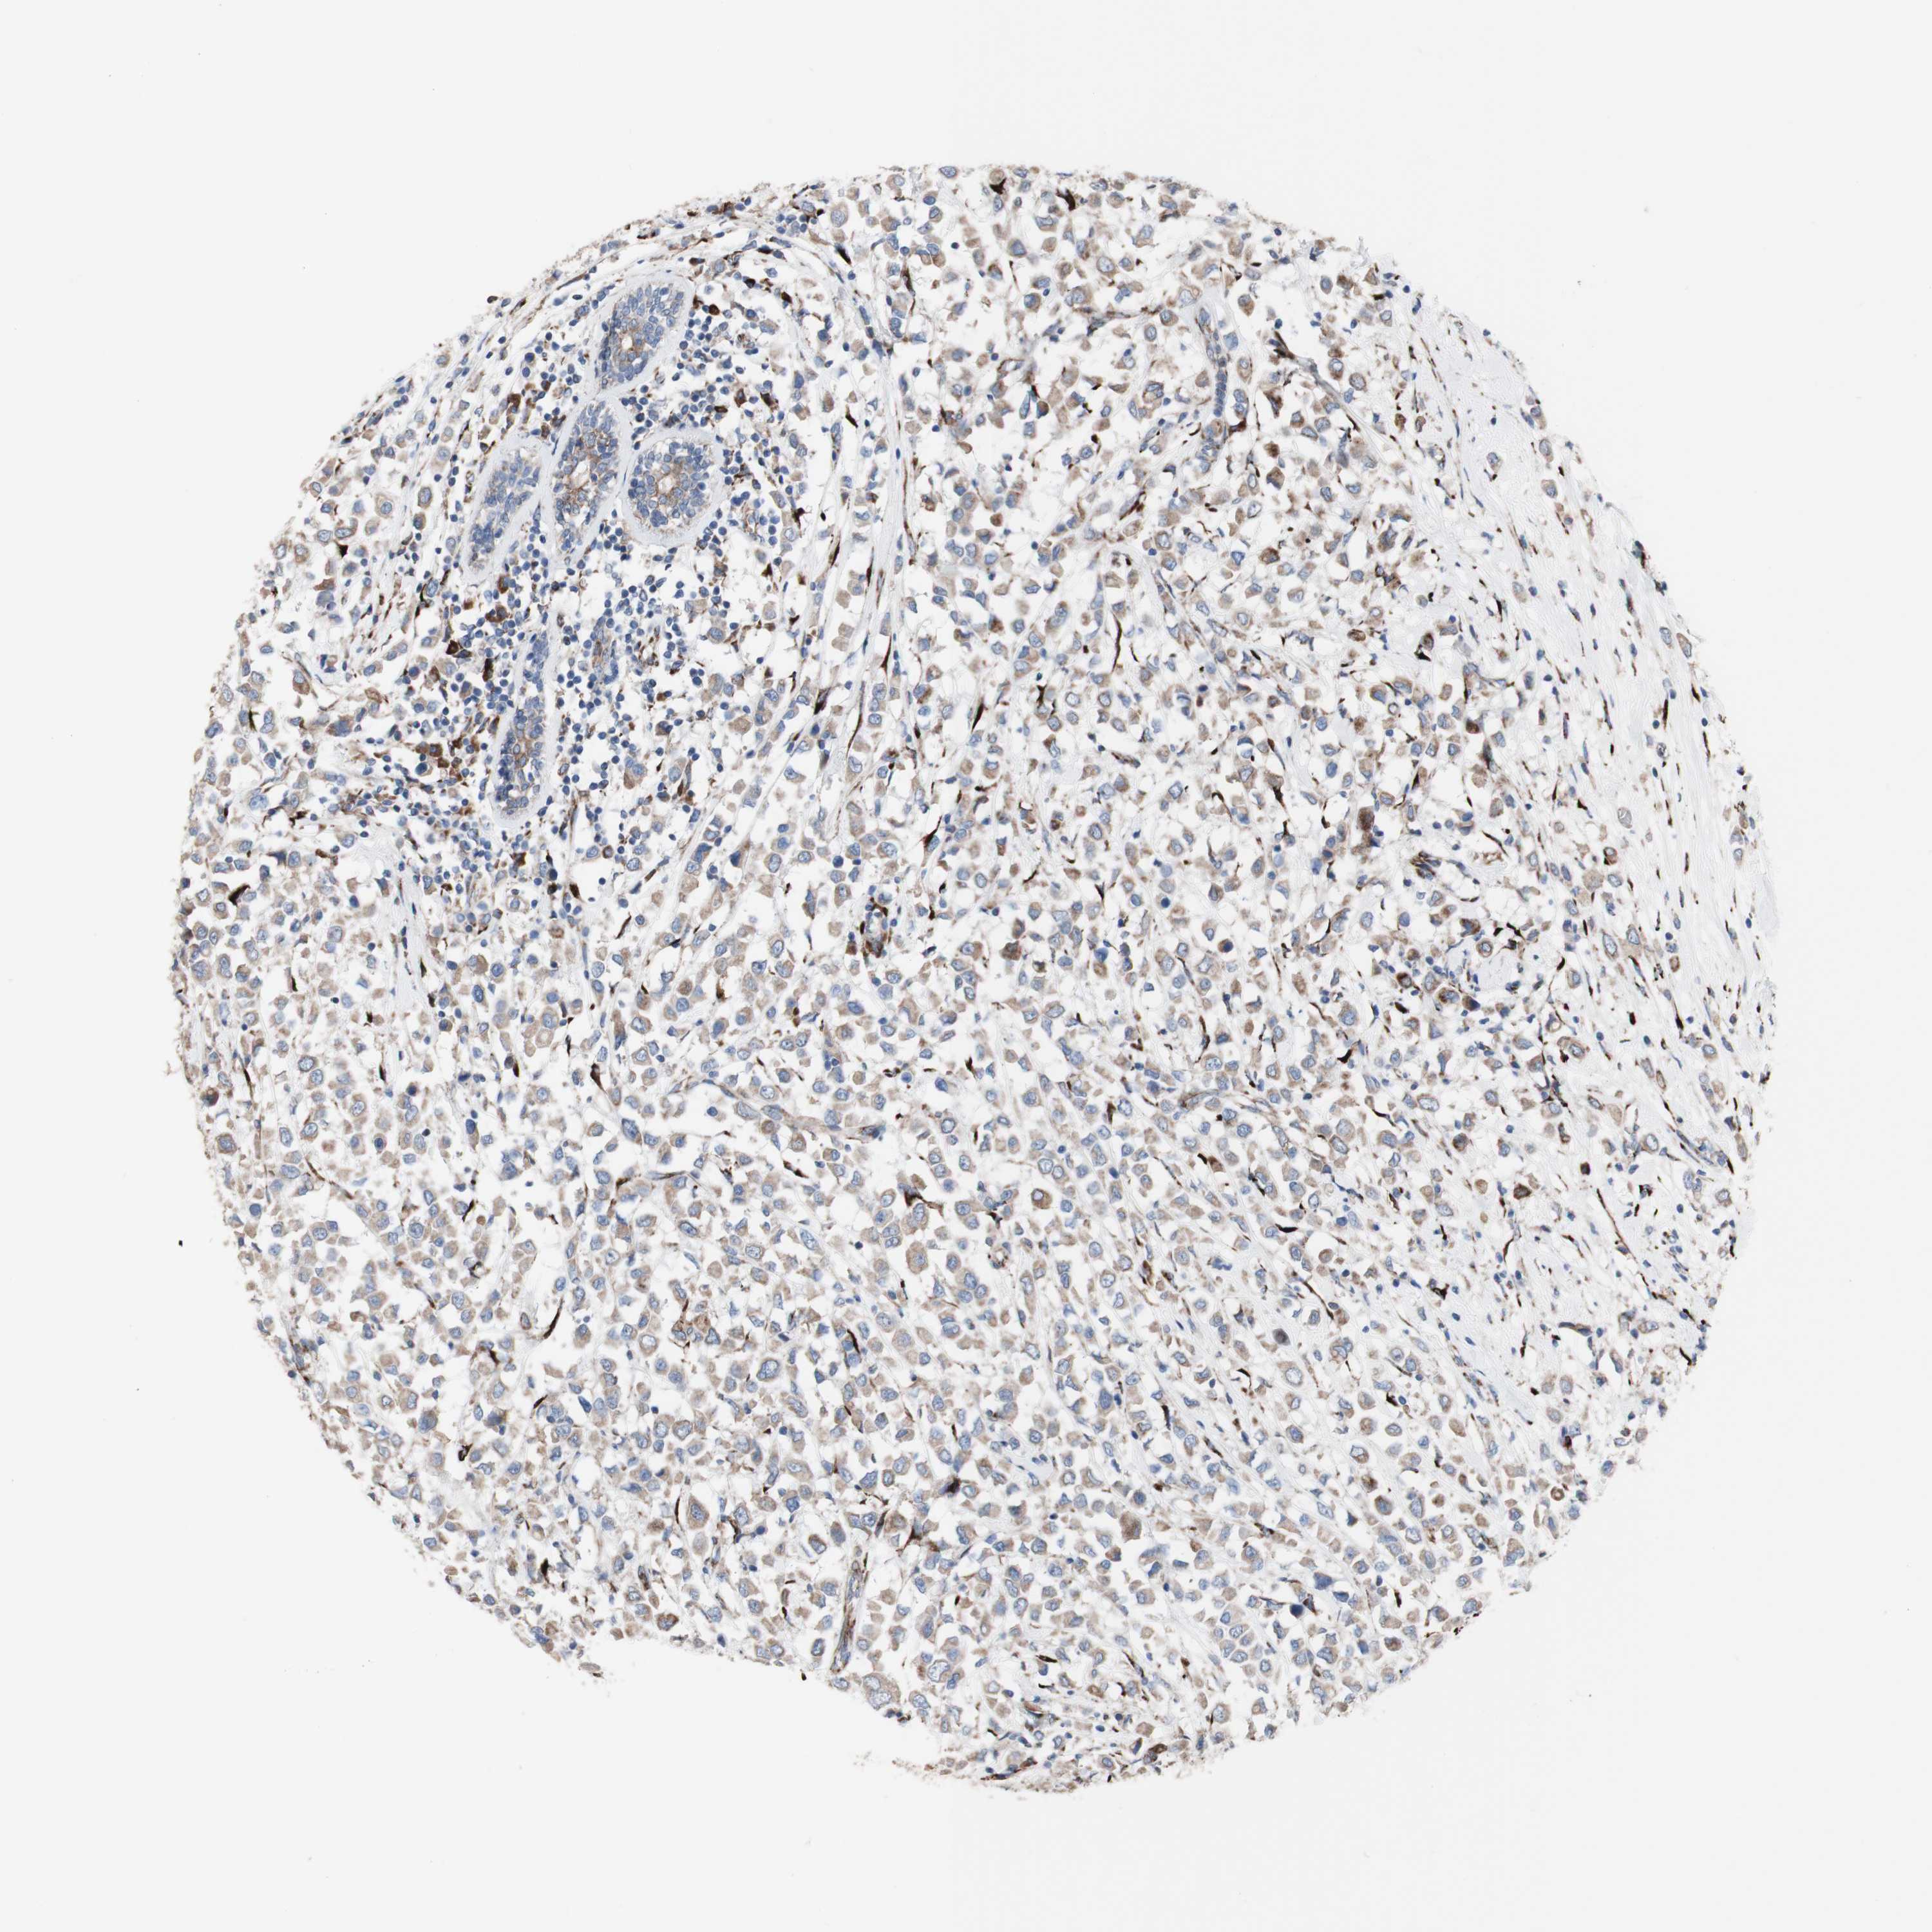

BRCA TCGA BRCA VALIDATION PROTEIN EXPRESSION

ANTIBODIES

AND

VALIDATION